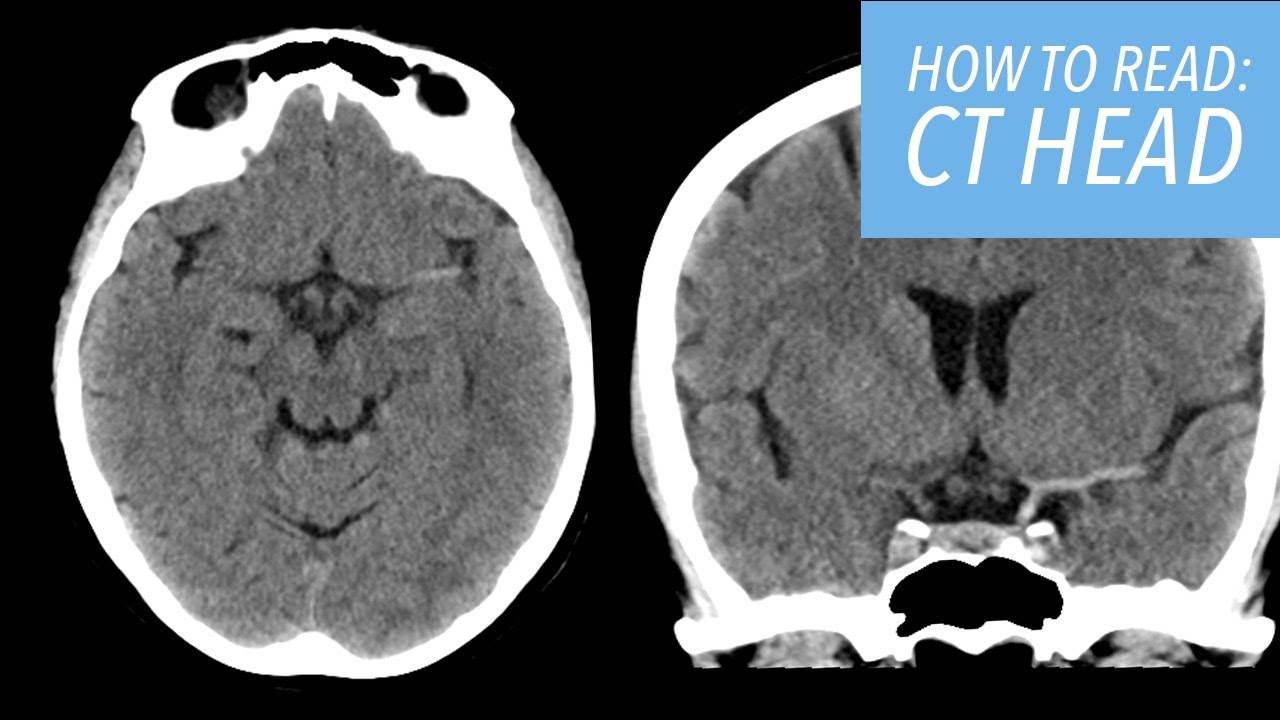

A Systematic Approach To The Interpretation Of Ct Head This presentation provides a systematic approach to analyzing head ct scans. it begins with identifying basic information about the patient and study parameters. The ct head scan is one of the most common imaging studies you can be faced with and the most frequently requested by the emergency department. this article will cover some of the underlying principles of ct head studies and discuss a method for their interpretation. The use of ct for the evaluation of head injuries and mental status changes is common. radiologists must have a reliable system for evaluating a head ct scan, which will improve. Interpret head ct scans using a structured, anatomic checklist method that systematically evaluates blood, brain, cisterns, ventricles, and bone—this approach reduces missed diagnoses and ensures comprehensive assessment regardless of clinical presentation. 1.

A Systematic Approach To The Interpretation Of Ct Head The use of ct for the evaluation of head injuries and mental status changes is common. radiologists must have a reliable system for evaluating a head ct scan, which will improve. Interpret head ct scans using a structured, anatomic checklist method that systematically evaluates blood, brain, cisterns, ventricles, and bone—this approach reduces missed diagnoses and ensures comprehensive assessment regardless of clinical presentation. 1. In this review, we discuss current methods and applications of quantitative analysis of head ct imaging. Error reporting solve: as a result of ever increasing unsanctioned scraping by bots, we have instituted a challenge designed to keep them out, and make sure real users get the best experience possible. if you're not a bot, you shouldn't see this error. if it persists, please contact [email protected] and we'll help to unblock you. A systematic approach to the interpretation of ct (computed tomography) of the head for the emergency physician. includes annotated images. Radiologists must have a reli able system for evaluating a head ct scan, which will improve diagnostic accuracy and speed of interpretation. this article discusses a systematic approach to head ct interpretation and review some of the common pathologies seen in clinical practice.